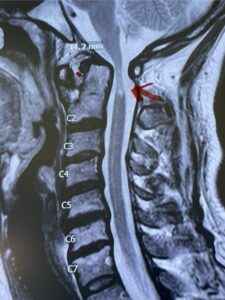

This is a 42 year-old female who presents with severe progressive weakness and numbness and difficulty with balance over a 6-month period. She has a history of having a motor vehicle accident at 5 years old but was never imaged. On exam she was noted to be severely myelopathic. Imaging revealed severe spinal cord compression at the level of C1 (Figs 4a and b).

Fig. 4a: Sagittal T2-weighted cervical MRI demonstrating severe cord compression with myelomalacia of upper cervical spinal cord (red arrow). Notice the increased atlanto-dens interval (red dot).